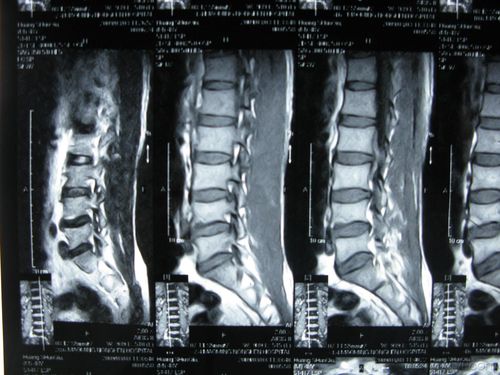

腰椎椎管占位请大家会诊附有ct图片